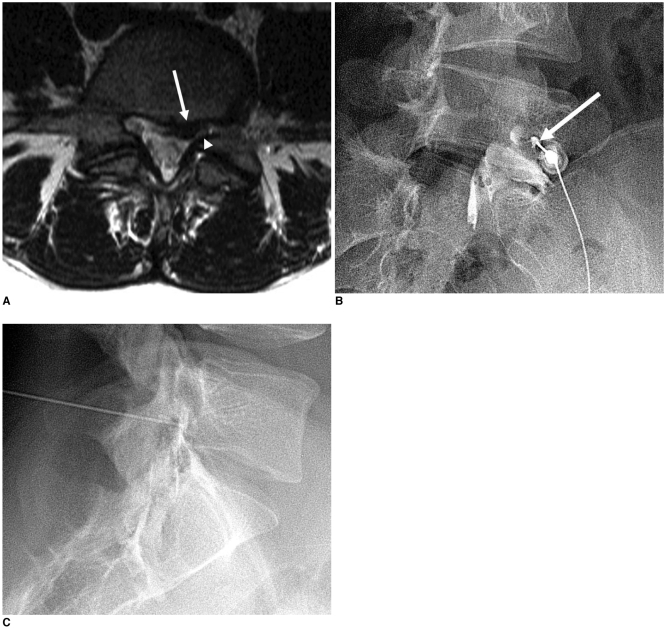

Three fluoroscopic contrast patterns during L5 selective nerve root block: Type 1 (contrast along nerve root), Type 2 (contrast in foramen but not around root), Type 3 (no root or foramen contrast). Pattern type affects diagnostic reliability.

4. Contrast injection first: Inject 0.1-0.3 mL of contrast to confirm position and observe the spread pattern — critical to verify limited, localized spread

• Contrast injection before anesthetic confirms that the spread pattern is limited to the target nerve

• Inject 0.2-0.3 mL of contrast first to verify limited spread to the target nerve only

• Evaluate contrast flow carefully — spread beyond the targeted spinal nerve either centrally into the foramen or laterally to the plexus increases the false-positive likelihood

• Evaluate contrast flow for any spread beyond the targeted spinal nerve

• Contrast injection (0.1-0.3 mL) before anesthetic confirms limited spread to the target nerve